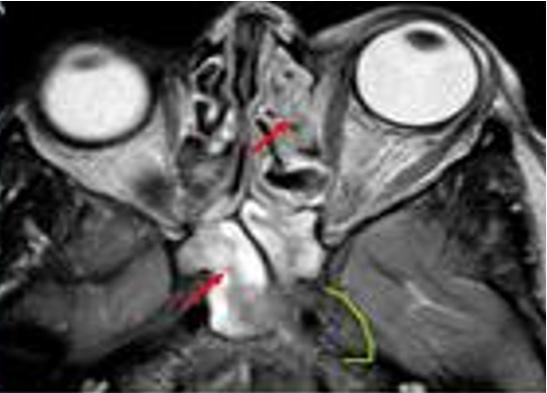

DIAGNÓSTICO

produciendo proptosis axial, hipermetropía y pliegues coroideos.

La escisión quirúrgica suele tener éxito y está indicada si el paciente presenta síntomas.

Figura 84. Figura 85. Imagen de resonancia magnética axial del hemangioma cavernoso intraconal de la órbita izquierda colindante con el nervio óptico.